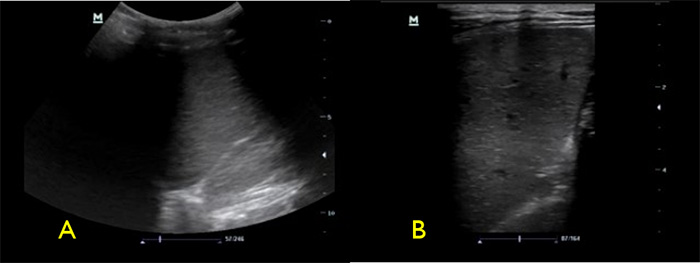

- Fan the transducer through the spleen to evaluate for focal splenic lesions.

- If no lesions are noted, switch to the high frequency linear transducer to evaluate the spleen for small focal hypoechoic lesions. (Video 5)

Figure 4. Spleen with low frequency (A) vs high frequency (B) transducers